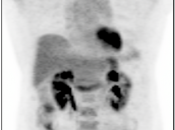

3. Excellent Views: The MIP, Coronal & Sagittal Images

- 3-D Rotating MIP & Coronal “Quick MIP”

- Coronal PET